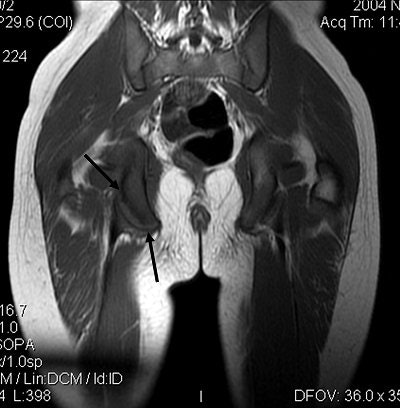

Plain radiographs, including an anteroposterior view of the pelvis, showed an avulsion of the right ischial tuberosity in the typical inferolateral location. An MR exam demonstrated osseous and soft-tissue edema, along with an avulsion fracture of the right ischial tuberosity (Figures 1-4).

Figure 4. Coronal T1-weighted MR image optimally shows the fracture line between the ischial tuberosity fracture fragment and the remainder of the ischium (black arrows). All images courtesy of Adam D. Sharp and Dr. Douglas Beall.